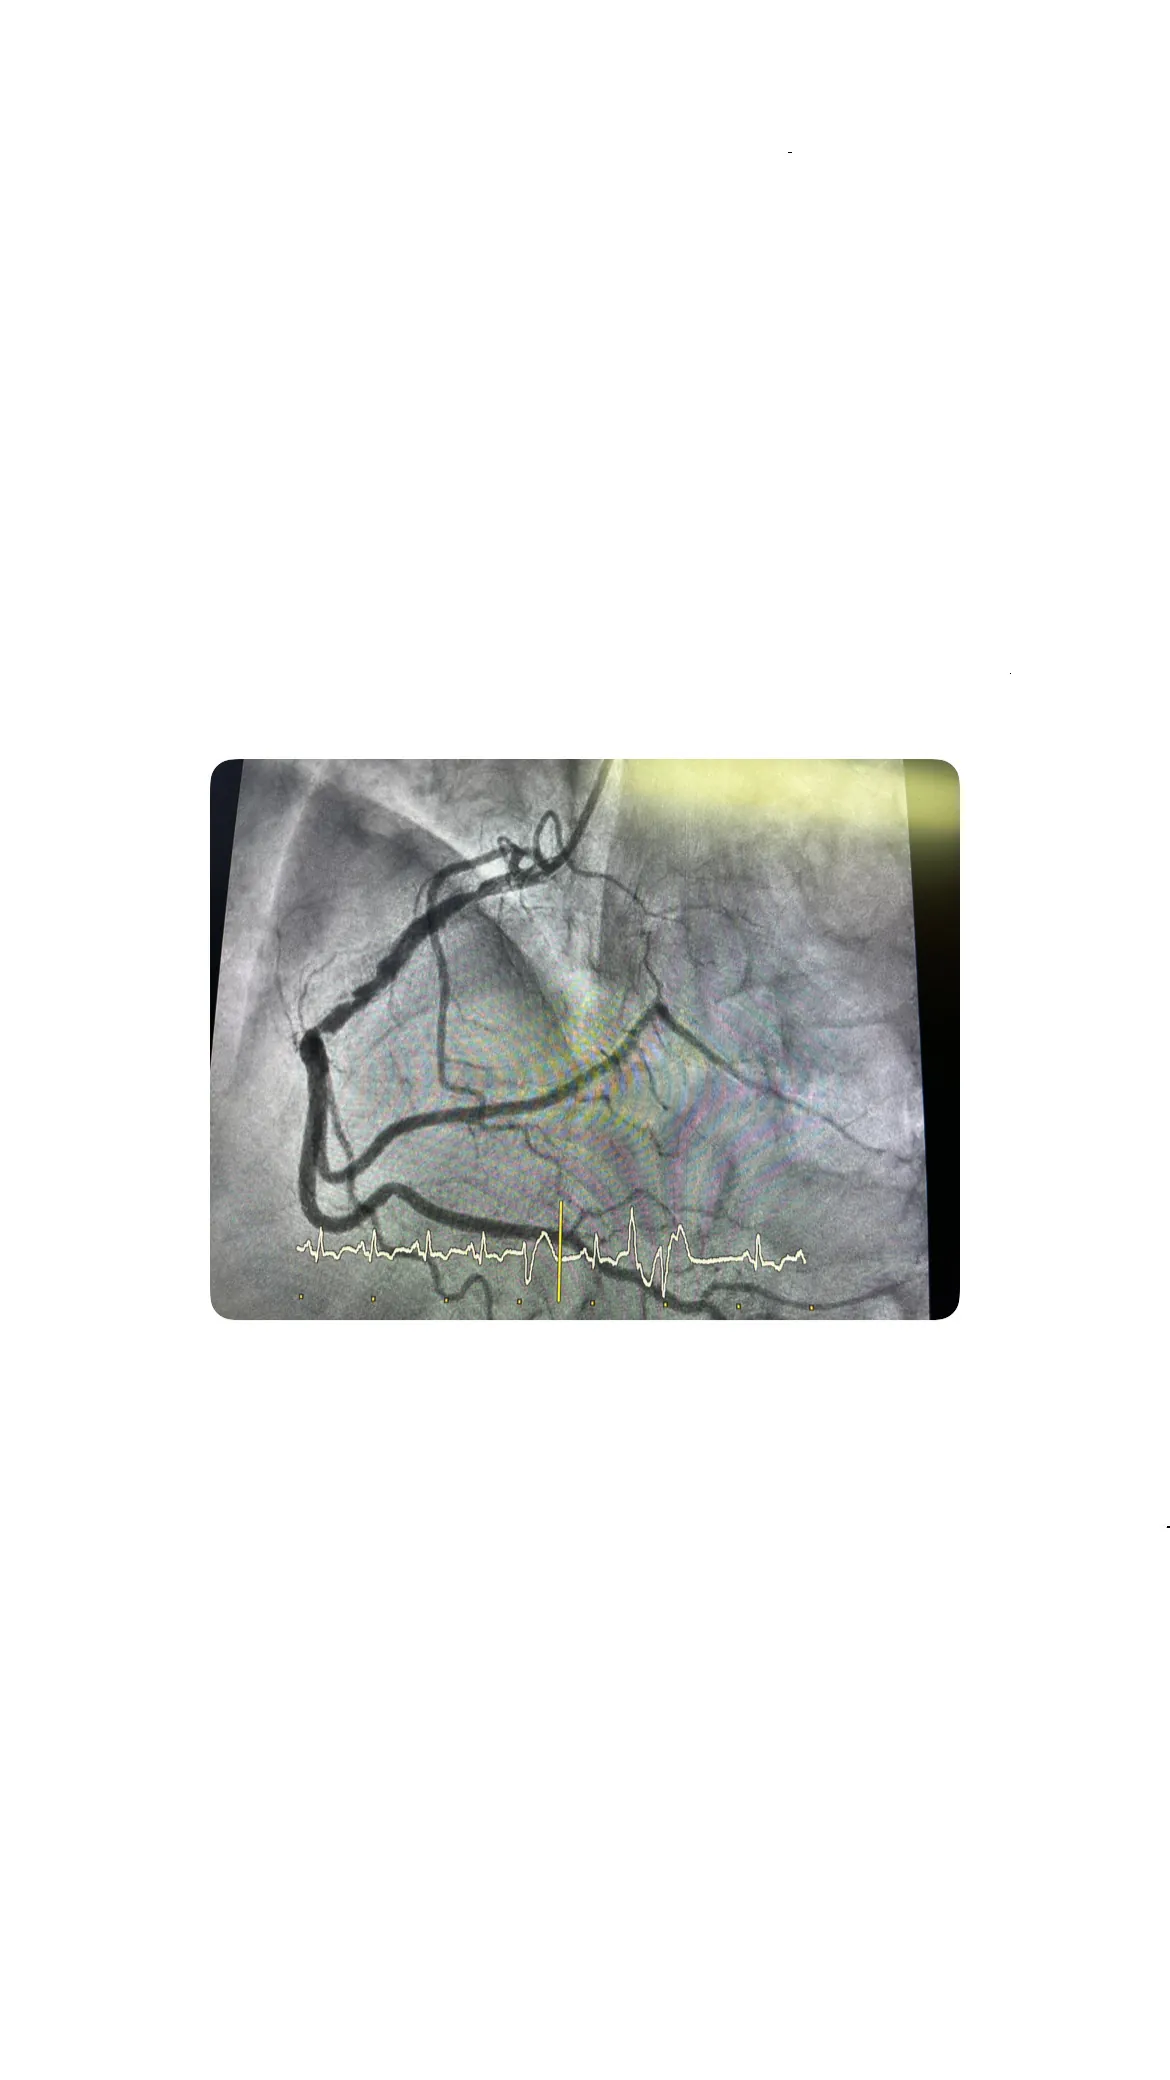

Tratamiento de la lesión: predilatación y balón farmacoactivo

Implantación de balón farmacoactivo y resultado del procedimiento

La implantación del balón farmacoactivo fue exitosa y el paciente toleró bien el procedimiento. Este tipo de balón libera medicamentos que ayudan a prevenir la reestenosis, mejorando así el pronóstico a largo plazo y reduciendo el riesgo de futuras complicaciones.